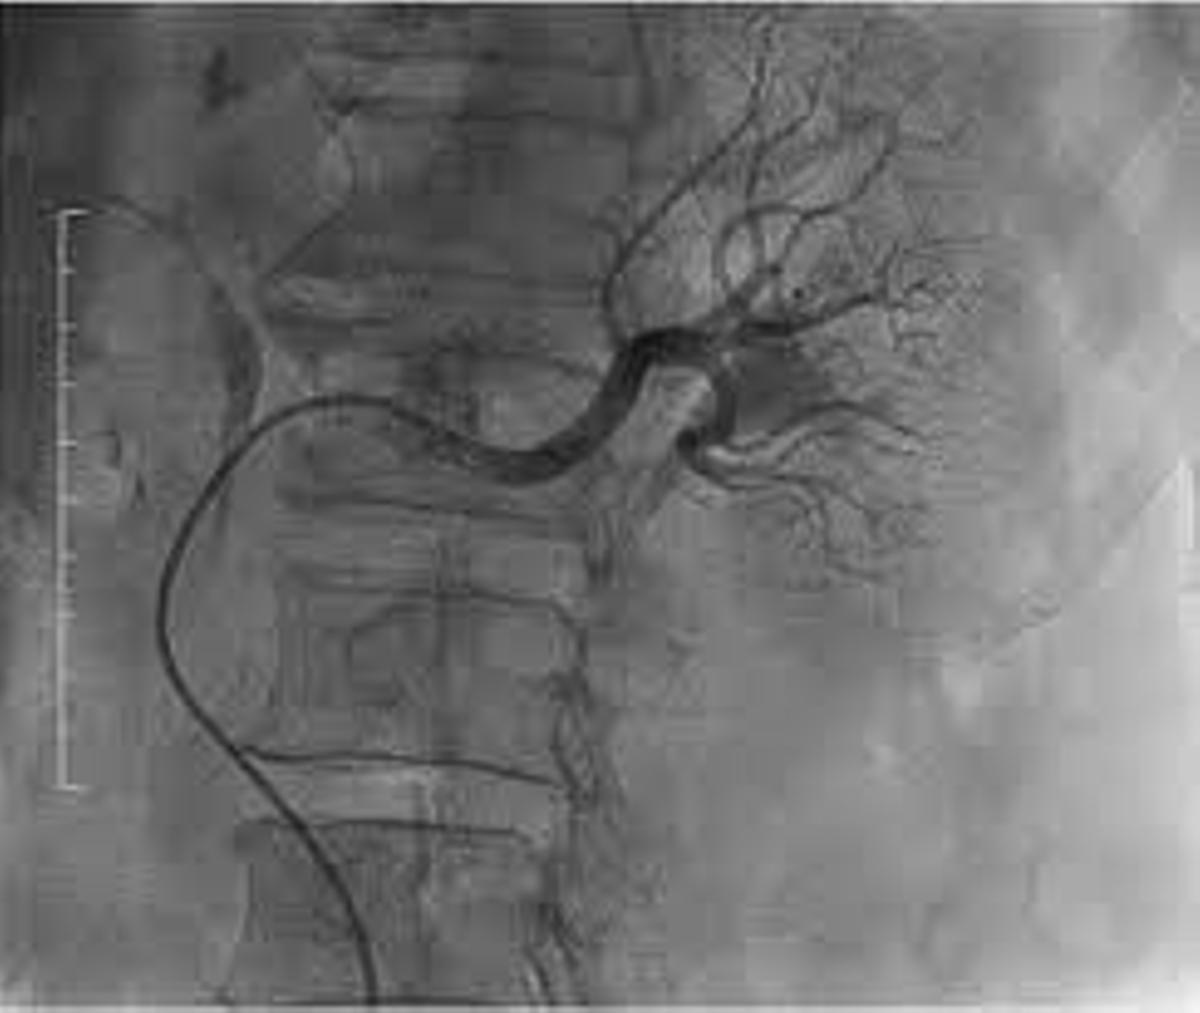

La denervación renal mejora la efectividad clínica. / Juaneda Hospitales

La denervación de arterias renales es un procedimiento hemodinámico. El especialista, mediante una punción mínimamente invasiva accede a la arteria femoral, introduciendo un catéter que guía hasta las arterias renales, auxiliado por una angiografía (Rayos X) que permite identificar las arterias diana y actuar sobre el sistema nervioso que las rodea.

«Esta intervención —añade el Dr. Vergara— ha evolucionado tecnológicamente en los últimos años, mejorando su efectividad clínica, pasando de utilizarse un catéter con un único electrodo a otro con cuatro. Esos electrodos transmiten radiofrecuencia generadora de calor a la pared arterial provocando la ablación de los nervios periféricos».